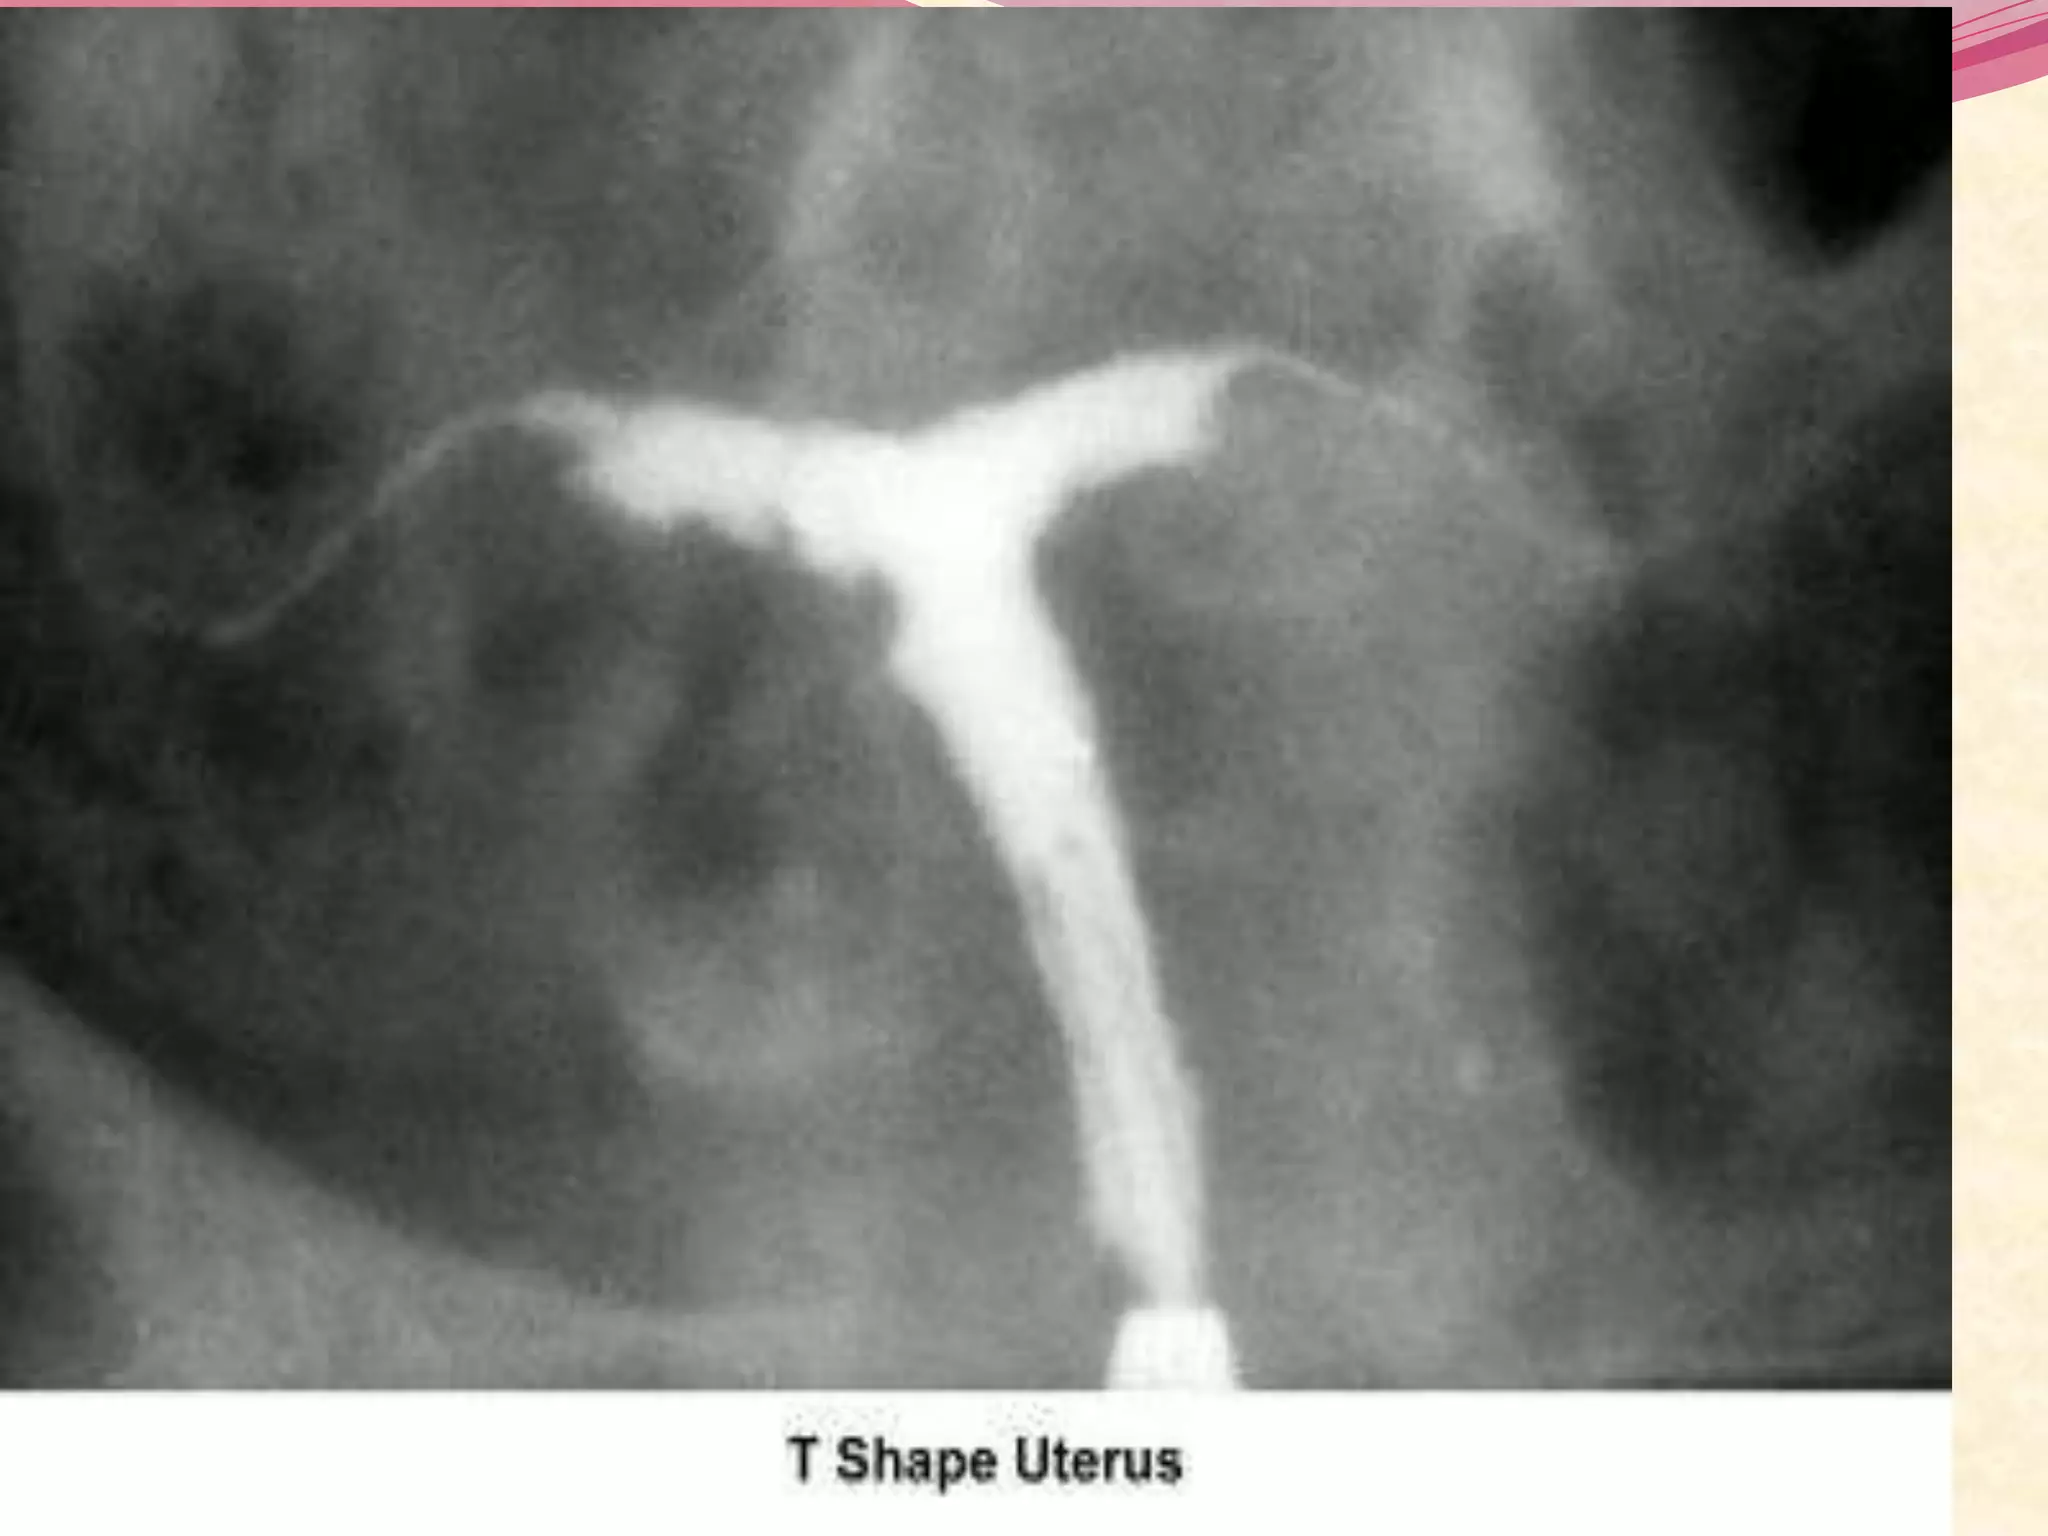

 The most common uterine malformations observed

during the past 40 years were drug induced. From

the late 1950s until the early 1970s, diethylstilbestrol

(DES) was used to treat patients with a history of

recurrent abortion .

 Later in life, these so-called DES daughters are

found to have T-shaped uteri that result in infertility,

recurrent miscarriage, and preterm

deliveries. malfunction of the fallopian tubes,

menstrual irregularities, and the development of

clear cell carcinoma of the vagina.

I. Hysterosalpingogram :

 The HSG is the most frequently used diagnostic tool

to evaluate the endometrial cavity.

 provides accurate information about the :

o endocervical canal

o diameter and configuration of the internal os

o endometrial cavity

o uterine/tubal junction (cornual ostium)

o diameter, location, and direction of the fallopian tubes

o status of the fimbriae

o spill into the endometrial cavity.

 Abnormal finding include :

o Congenital malformation of the uterus.

o Submucous leiomyomas

o Intrauterine synechiae (asherman syndrome)

o Intrauterine polyps

o Proximal or distal tubal occlusion .

o Salpingitis isthmica nodusa